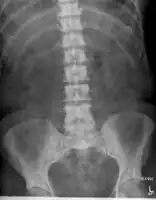

The most important distinction made by any staging system is whether the cancer is confined to the prostate. In the TNM system, clinical T1 and T2 cancers are found only in the prostate, while T3 and T4 cancers have metastasized. Several tests can be used to look for evidence of spread. Medical specialty professional organizations recommend against the use of PET scans, CT scans, or bone scans when a physician stages early prostate cancer with low risk for metastasis.[95] Those tests would be appropriate in cases such as when a CT scan evaluates spread within the pelvis, a bone scan looks for spread to the bones, and endorectal coil magnetic resonance imaging evaluates the prostatic capsule and the seminal vesicles. Bone scans should reveal osteoblastic appearance due to increased bone density in the areas of bone metastasis—the reverse of what is found in many other metastatic cancers.

Sclerosis of the bones of the thoracic spine due to prostate cancer metastases (CT image) -

Sclerosis of the bones of the pelvis due to prostate cancer metastases